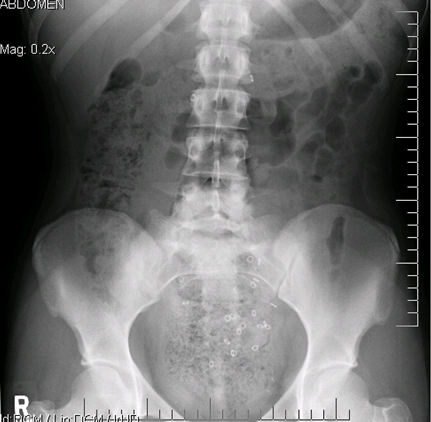

Radiografia abdominal simples (incluindo as incidências ortostática e em decúbito lateral [cross-table]): deve ser obtida em caso de suspeita de obstrução intestinal.[Figure caption and citation for the preceding image starts]: Radiografia abdominal mostrando impactação fecal em um paciente com constipaçãoDos acervos do Dr. R.A. Gomez-Suarez e Dr. J.E. Fortunato; usado com permissão [Citation ends].